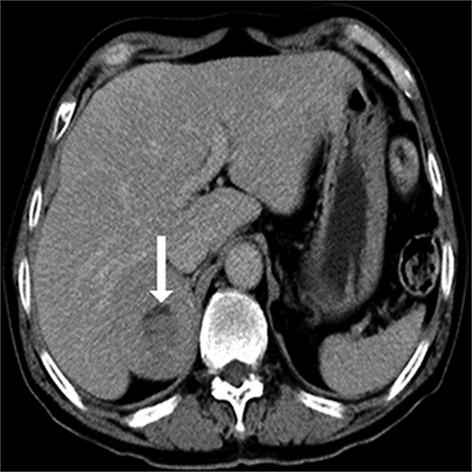

• 嗜铬细胞瘤及副神经节瘤不同生化表型的CT征象对比研究

2024, 49(2):203-209. DOI: 10.13406/j.cnki.cyxb.003433

摘要 (51) HTML (33) PDF 3.10 M (96) 评论 (0) 收藏

摘要:目的 分析生化阴性嗜铬细胞瘤及副神经节瘤(pheochromocytomas and paragangliomas,PPGLs)的电子计算机断层扫描(computed tomography,CT)征象是否有别于生化阳性PPGLs,同时了解生化阳性PPGLs不同表型的CT征象是否存在差异。方法 回顾性分析131例PPGLs患者的术前腹部增强CT图像,包括肿瘤位置、大小、形态、囊变坏死、液-液分层、钙化、向心结节状强化、肿瘤内粗大血管、强化包膜、绝对廓清率及相对廓清率。根据生化水平,将患者分为生化阳性组和阴性组,阳性组进一步分为去甲肾上腺素型、肾上腺素型及多巴胺型。比较各组及各表型间的CT征象差异。结果 相较于生化阴性组,阳性组PPGLs更大(Z=-2.064,P=0.039)、囊变坏死(χ2=6.610,P=0.010)及向心结节状强化(χ2=3.909,P=0.048)的比例更高;相较于去甲肾上腺素型,肾上腺素型PPGLs更大(Z=-2.036,P=0.042)、强化包膜比例更高(χ2=7.242,P=0.007)。结论 肿瘤大小、囊变坏死及向心结节状强化的CT征象有助于术前诊断生化阴性PPGLs,肿瘤大小及强化包膜有助于解释去甲肾上腺素型及肾上腺素型PPGLs不同临床表现产生的机制。